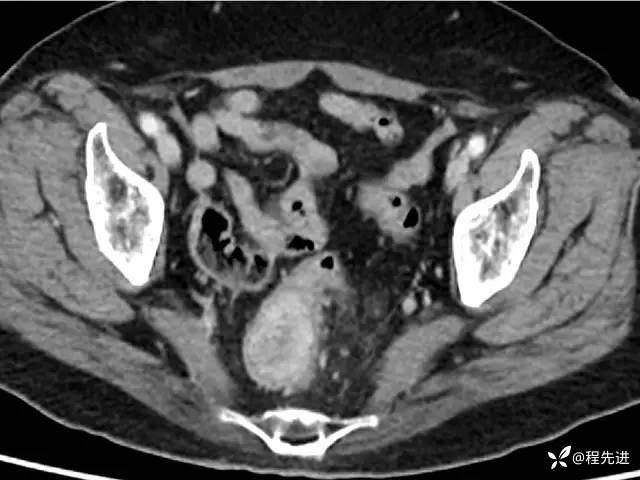

CT平扫:

CT增强: